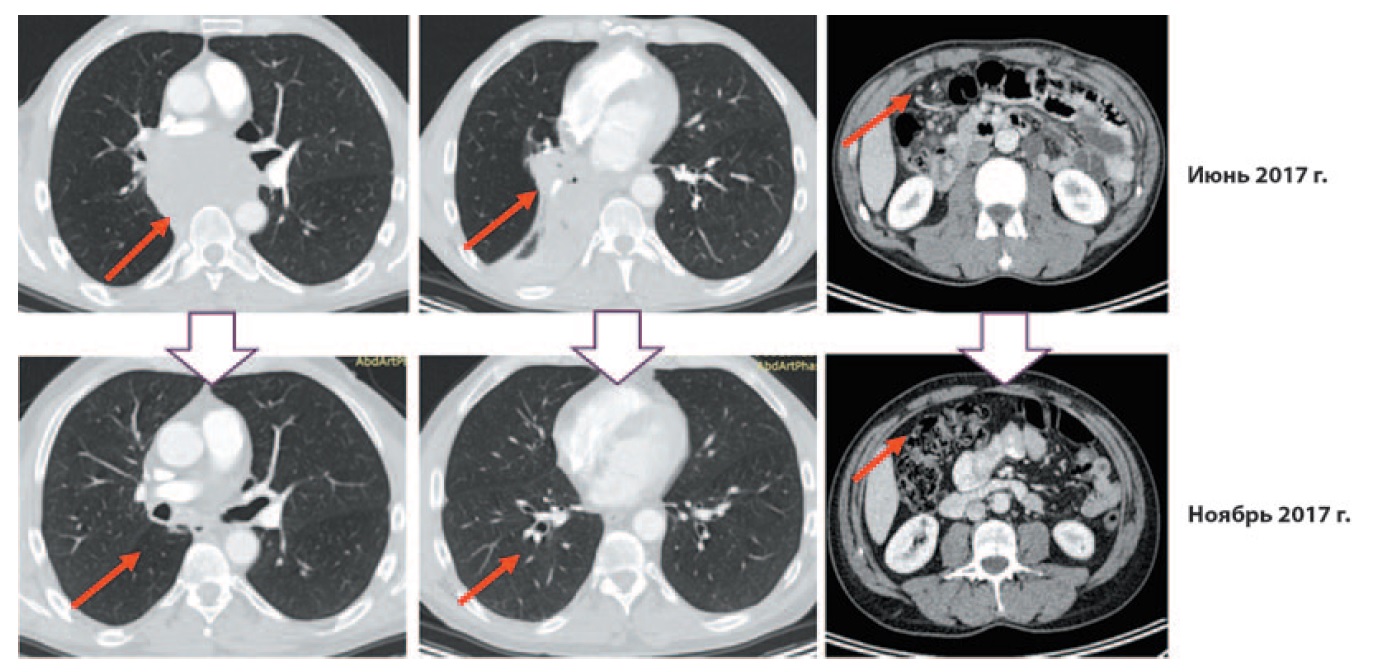

При контрольной МСКТ от ноября 2017 г. (рис. 4) сохранялись отдельно расположенные фрагменты опухолевого конгломерата, размеры их несколько уменьшились: бифуркационных лимфоузлов – до 38×17 мм, бронхолегочных лимфоузлов – до 18×11 мм и до 17×11 мм. Другие таргетные очаги, по сравнению с предшествующими исследованиями, не определялись.

Рис. 4. МСКТ от ноября 2017 г. в сравнении с МСКТ от июня 2017 г. / Fig. 4. MCT – November 2017 by comparison with MCT – June 2017.

С целью стадирования заболевания в июне 2017 г. выполнена МСКТ головного мозга, органов грудной клетки, брюшной полости и малого таза (рис. 2). В области корня правого легкого с переходом на заднее средостение выявлен опухолевый конгломерат, состоящий из опухолевого узла без четких контуров и увеличенных сливающихся бронхолегочных, бифуркационных, параэзофагеальных лимфоузлов. Общие размеры конгломерата лимфоузлов составили 88×57 мм. Промежуточный, нижнезональный, среднедолевой бронх прослеживались фрагментарно. Также выявлен ателектаз нижней и средней долей правого легкого. Отмечено распространение процесса на правый главный и верхнедолевой бронх, область бифуркации трахеи. Конгломерат вызывал компрессию левого главного бронха и левого предсердия. Выявлены компрессия и признаки опухолевой инвазии правой легочной артерии (оттеснение и сужение на протяжении 24 мм). Также визуализированы отдельно расположенные неувеличенные внутригрудные лимфоузлы левой бронхолегочной и паратрахеальной группы и параэзофагеальный лимфоузел справа размером 20×18 мм. В области брюшины определялись неорганные узловые образования, накапливающие контрастный препарат, размерами до 8 мм. При МСКТ головного мозга выявлена венозная ангиома в левой лобной области.

Рис. 2. МСКТ до начала терапии (июнь 2017 г.). Центральный рак правого легкого с поражением правого нижнезонального бронха с переходом на среднедолевой, главный бронхи. Метастазы во внутригрудных лимфоузлах, нельзя исключить переход процесса на область бифуркации трахеи, правую легочную артерию. Неорганные узловые образования в брюшной полости – канцероматоз брюшины. / Fig. 2. Multispiral computed tomography (MCT) before the therapy (June 2017). Centrally located right lung cancer with the lesion on the right lower lobe bronchus with the damage of the middle lobe bronchus and the primary bronchi. Intrathoracic lymph nodes metastases, it is not inconceivable that the damage took the area of bifurcation of the trachea, the right pulmonary artery. Inorganic abdominal mass – peritoneal carcinomatosis.